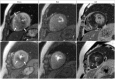

This document is the third part of the guidelines for the protocol, the interpretation and post-processing of cardiac magnetic resonance (CMR) studies. These consensus recommendations have been developed by the Consensus Committee of the Korean Society of Cardiovascular Imaging to standardize the requirements for image interpretation and post-processing of CMR. This third part of the recommendations describes tissue characterization modules, including perfusion, late gadolinium enhancement, and T1- and T2 mapping. Additionally, this document provides guidance for visual and quantitative assessment consisting of "What-to-See," "How-To," and common pitfalls for the analysis of each module. The Consensus Committee hopes that this document will contribute to the standardization of image interpretation and post-processing of CMR studies.